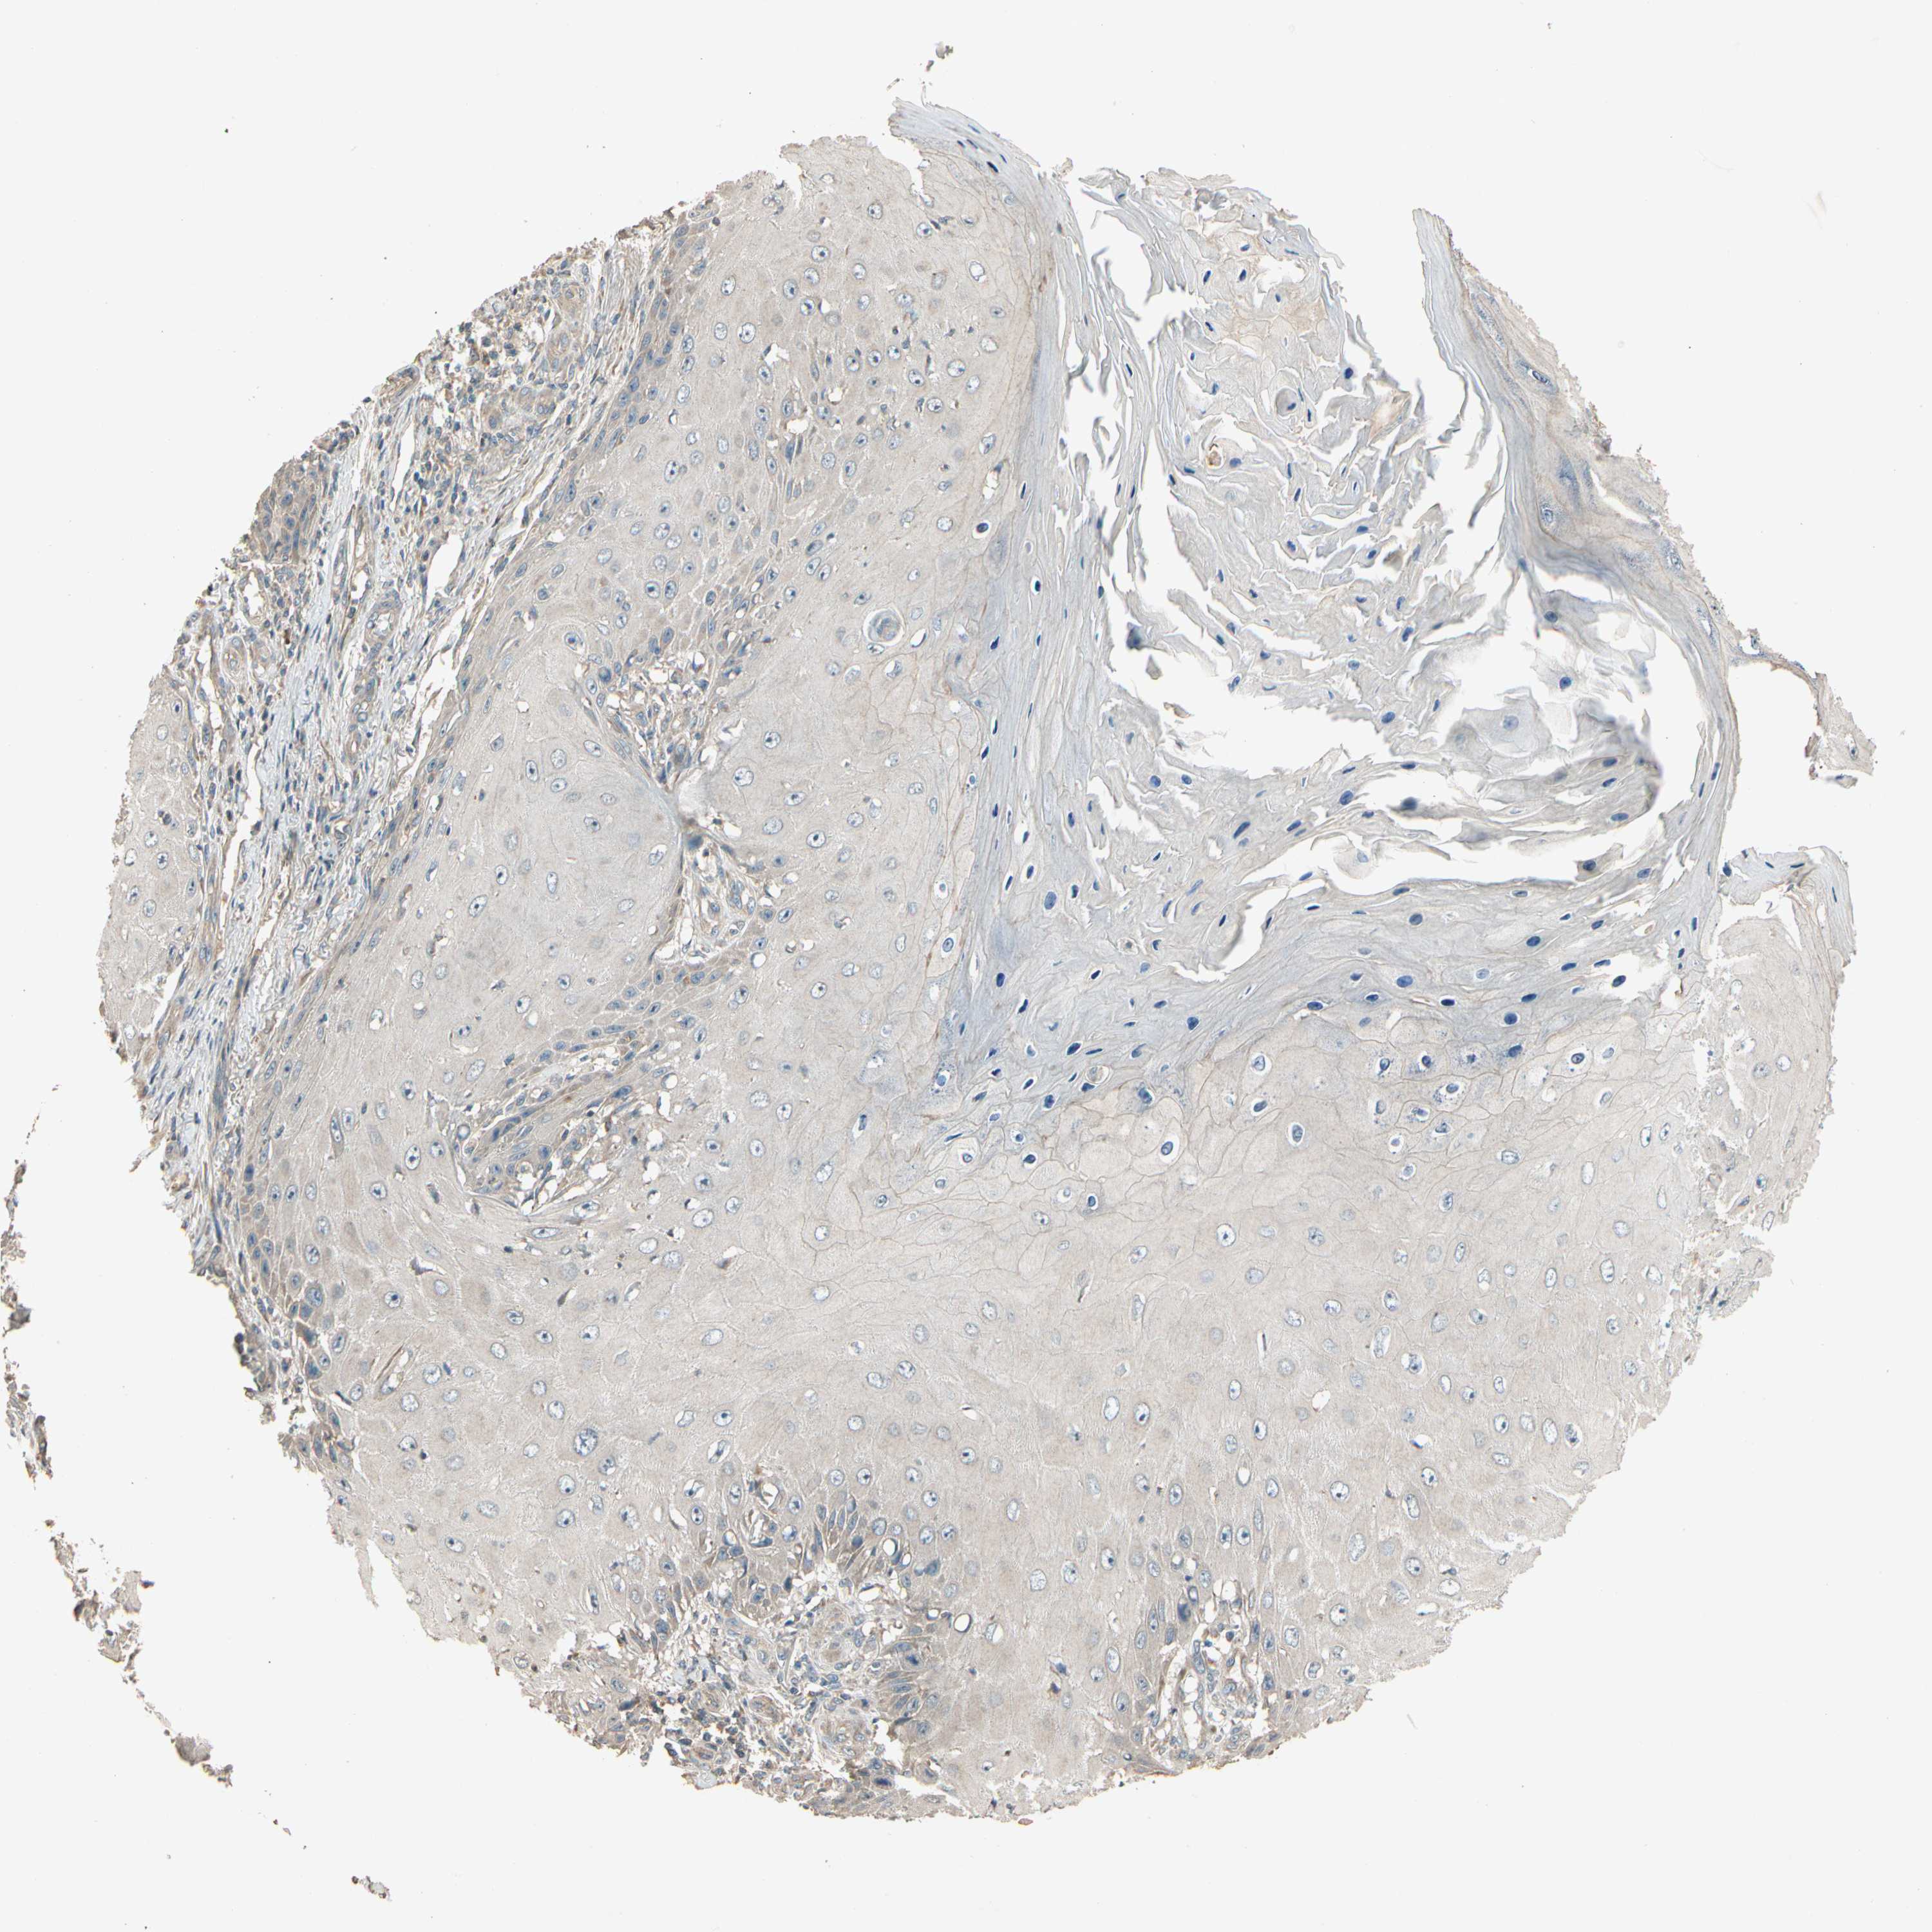

SKIN CANCER - Protein expressioni

A mouse-over function shows sample information and annotation data. Click on an image to view it in a full screen mode. Samples can be filtered based on level of antibody staining by selecting one or several of the following categories: high, medium, low and not detected. The assay and annotation is described here.

Antibody stainingi

Antibody staining in the annotated cell types in the current human tissue is reported as not detected, low, medium, or high, based on conventional immunohistochemistry profiling in selected tissues. This score is based on the combination of the staining intensity and fraction of stained cells.

Each image is clickable and will lead to virtual microscopy that enables deeper exploration of all samples and also displays staining intensity scores, fraction scores and subcellular localization as well as patient and tissue information for each sample.

Antibody HPA006746

Antibody CAB009805

Basal cell carcinoma

Adnexal tumor, benign